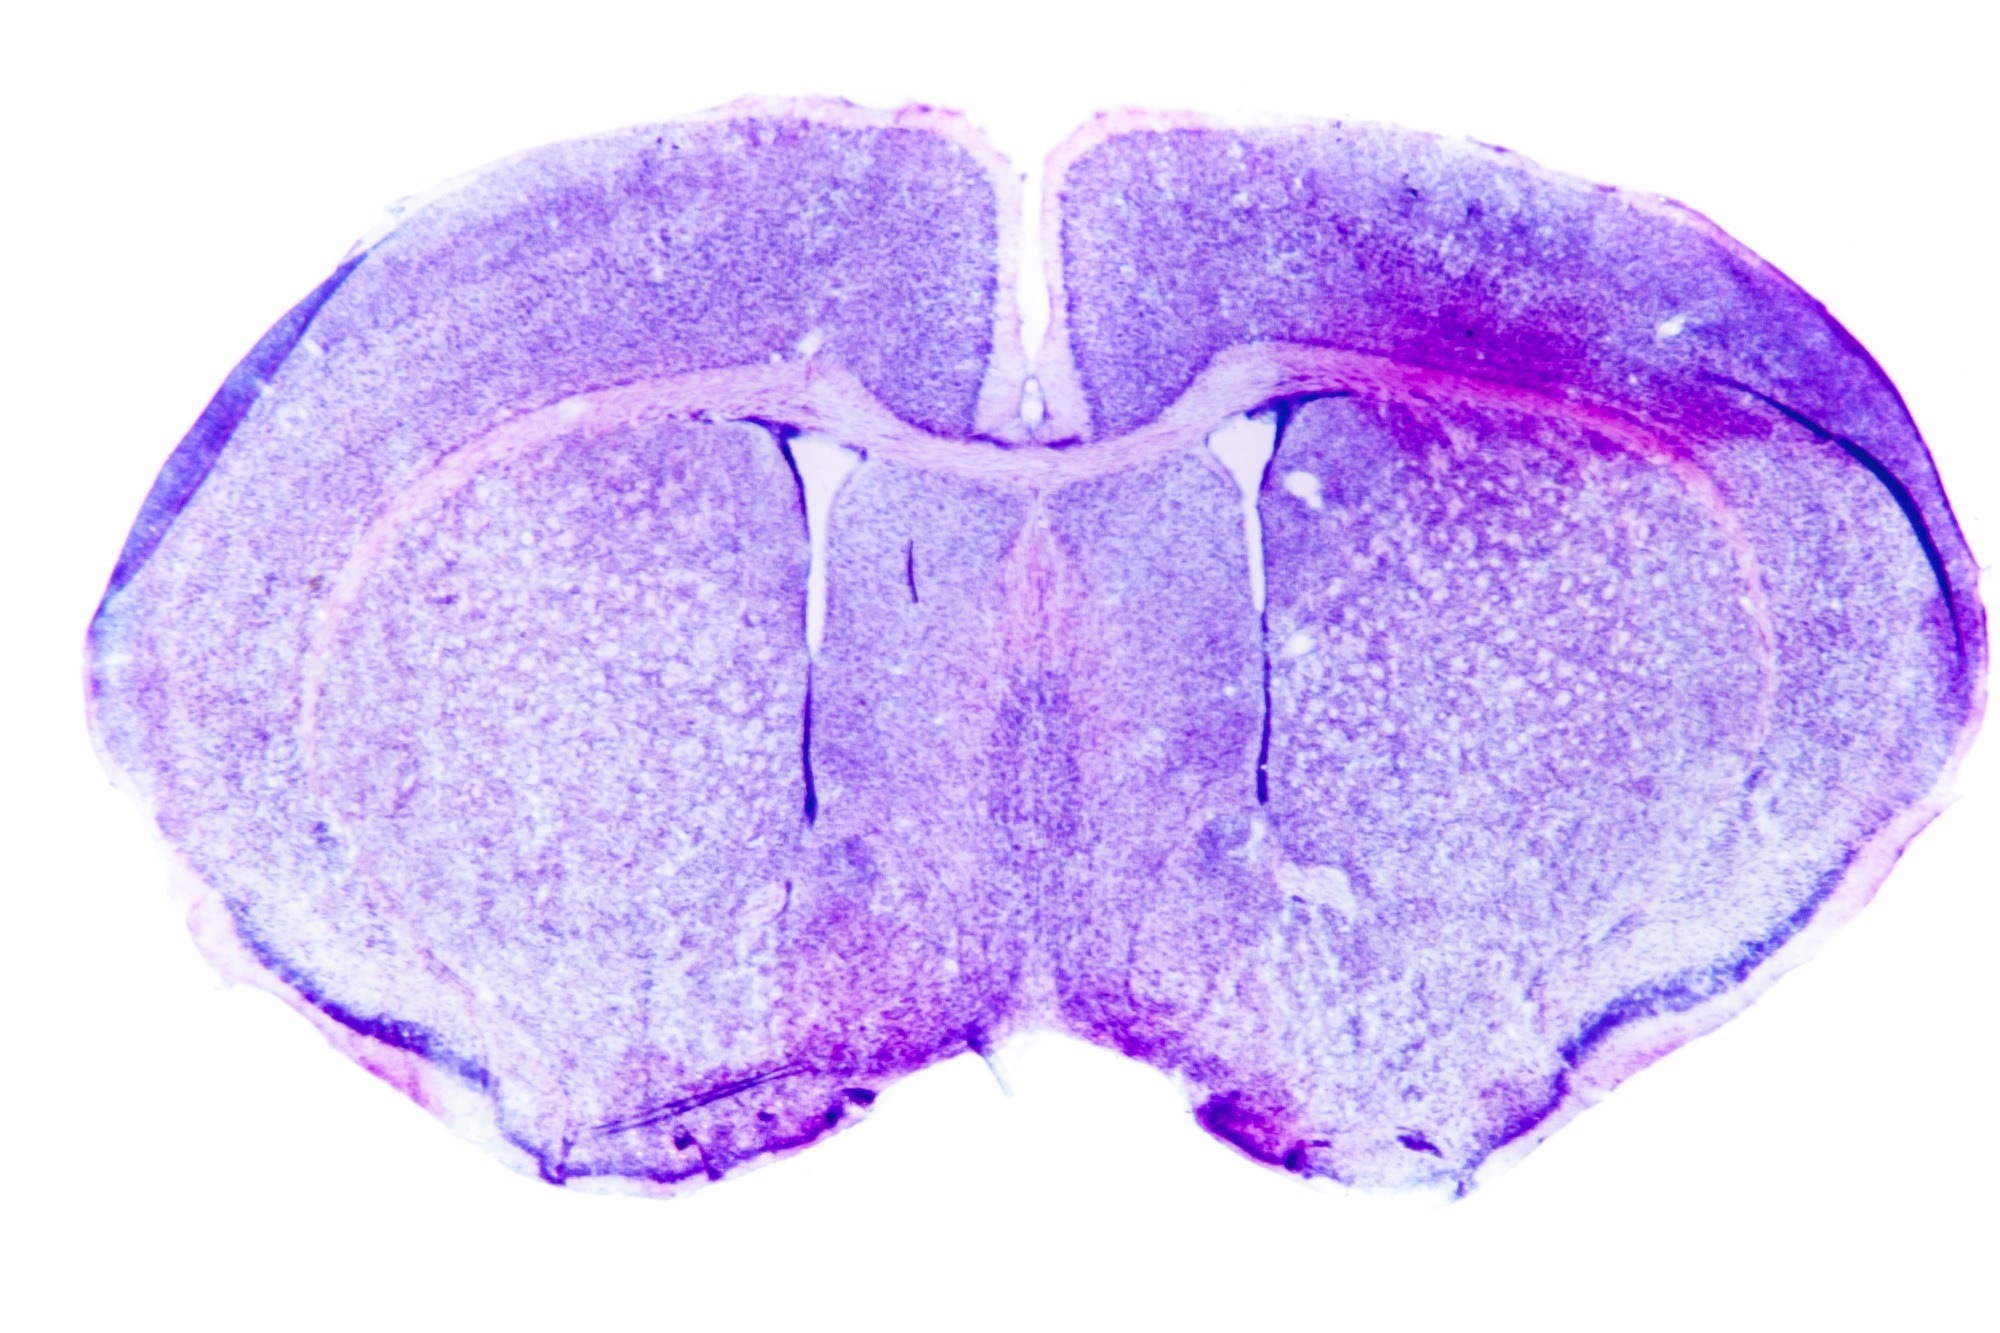

Micrograph of a rat brain. Image Credit: Pan Xunbin/Shutterstock.com